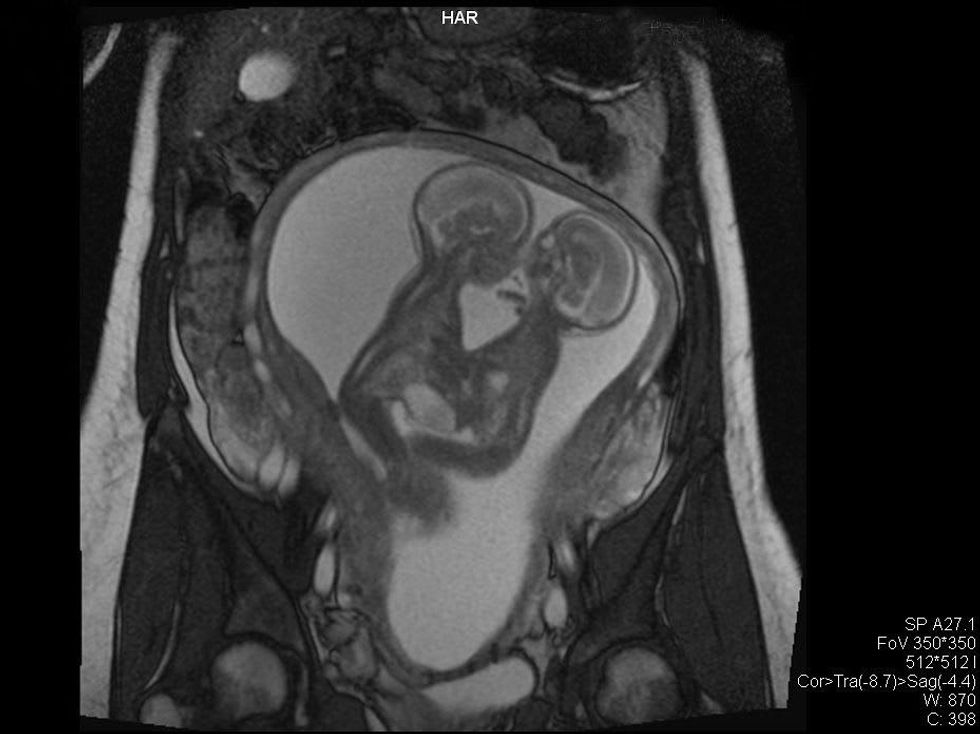

Dave and Jenni Ezell said making decisions about the complicated birth of their sons was the hardest thing they've ever had to do. After an MRI showed the twins were conjoined, the couple's first doctor recommended they abort the babies, because they had such a small chance of surviving.